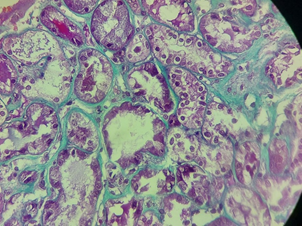

A skin biopsy was performed with IgM and C3 deposits associated with thrombocytopenia, bilirubin elevation, and acute renal failure, and the condition was compatible with aHUS Figure 1–5. Treatment with Intravenous Immune Globulin (IVIG) and Dexamethasone was started from 08/24 to 08/29/2023 and Eculizumab was started on 08/25/2023. A patient with prolonged hospitalization for three months, diagnosed with rare diseases, developed pulmonary thromboembolism, deep vein thrombosis of the right lower limb, and was anticoagulated with Apixaban. He was discharged and one month after discharge, he recovered his kidney function, using Ecolizumab, no longer requiring hemodialysis, in addition to the exchange of Apixabana for Marevan.

Figure 3 ThreeBiopsy - acute kidney failure - acute tubular necrosis III.

Kidney biopsy (August/2023)

Severe acute tubular necrosis.

Immunofluorescence negative for all antisera investigated.